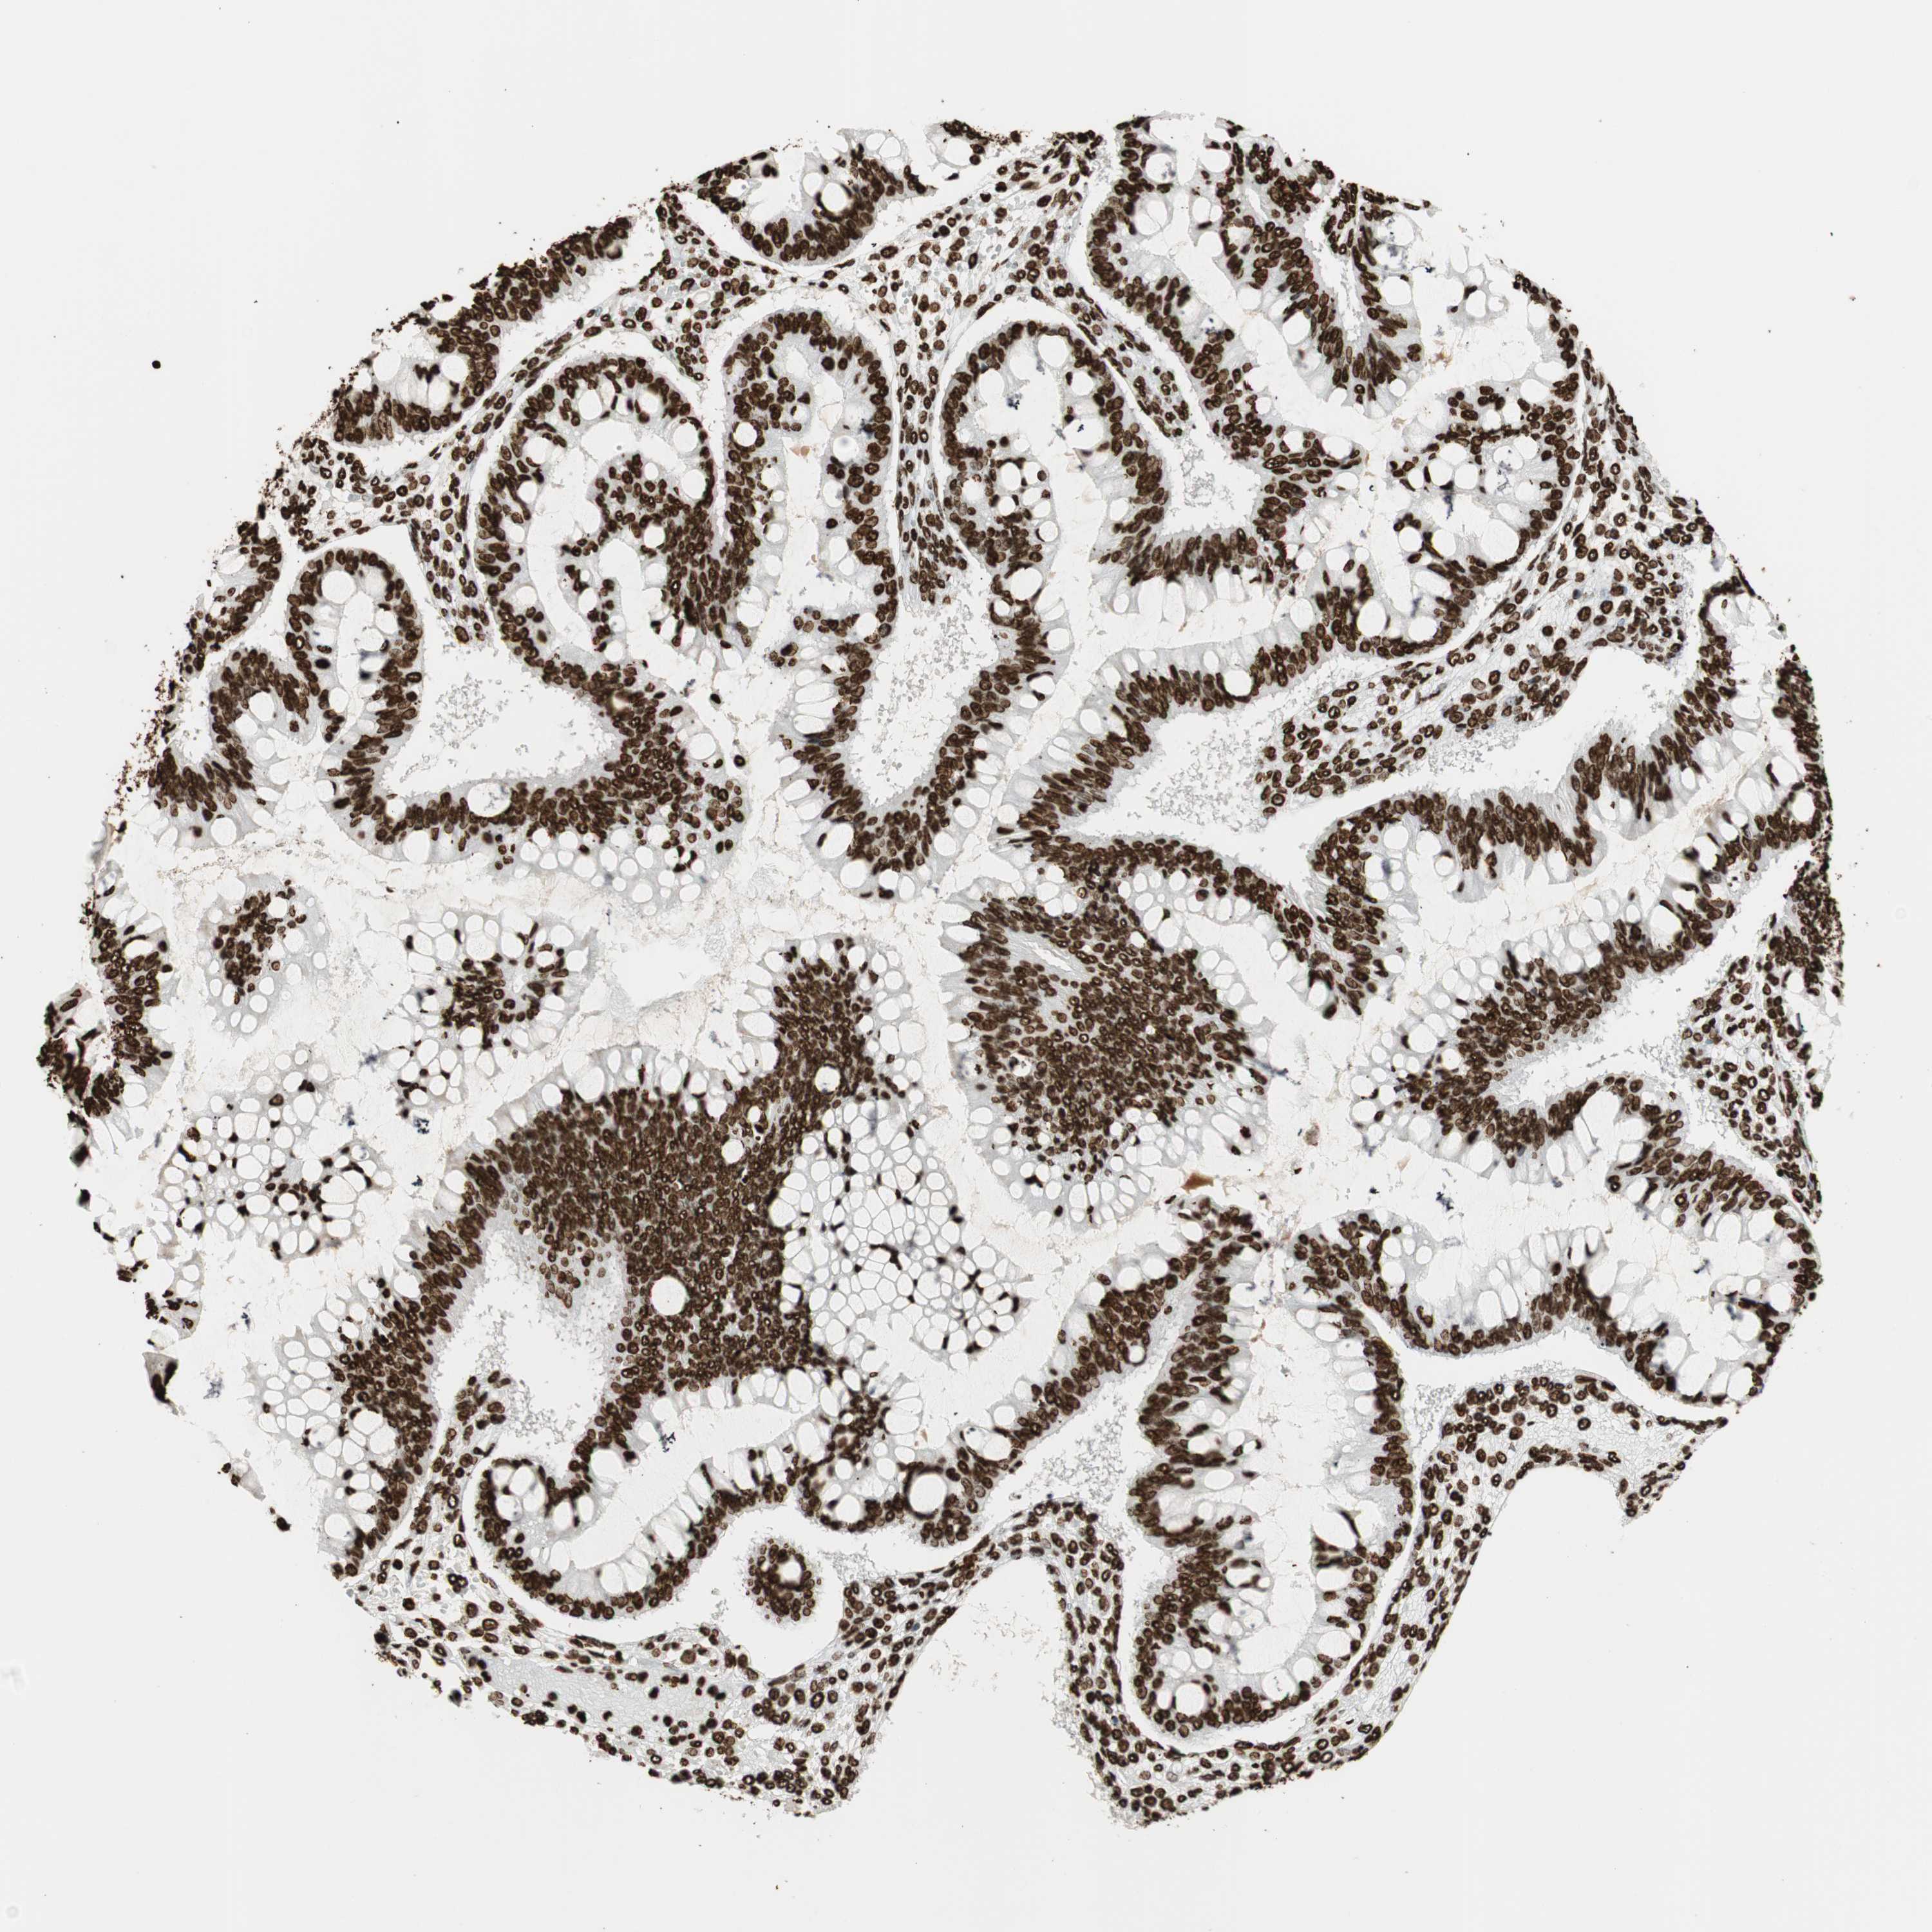

OVARIAN CANCER - Protein expressioni

A mouse-over function shows sample information and annotation data. Click on an image to view it in a full screen mode. Samples can be filtered based on level of antibody staining by selecting one or several of the following categories: high, medium, low and not detected. The assay and annotation is described here.

Note that samples used for immunohistochemistry by the Human Protein Atlas do not correspond to samples in the TCGA dataset.

Antibody stainingi

Antibody staining in the annotated cell types in the current human tissue is reported as not detected, low, medium, or high, based on conventional immunohistochemistry profiling in selected tissues. This score is based on the combination of the staining intensity and fraction of stained cells.

Each image is clickable and will lead to virtual microscopy that enables deeper exploration of all samples and also displays staining intensity scores, fraction scores and subcellular localization as well as patient and tissue information for each sample.

Antibody CAB008558

Staining

High

Medium

Low

Not detected

Intensity

Strong

Moderate

Weak

Negative

Quantity

>75%

75%-25%

<25%

None

Location

Nuclear

Cytoplasmic/membranous

Cytoplasmic/membranous,nuclear

Cystadenocarcinoma, serous, NOS

Carcinoma, endometroid

Cystadenocarcinoma, mucinous, NOS

Carcinoma, NOS